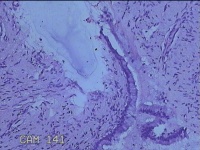

宫颈6点组织

性别

女

年龄

28岁

临床诊断

子宫颈上皮瘤样病变

一般病史

无

标本名称

大体所见

灰白暗红色组织1x0.3x0.2cm一块。